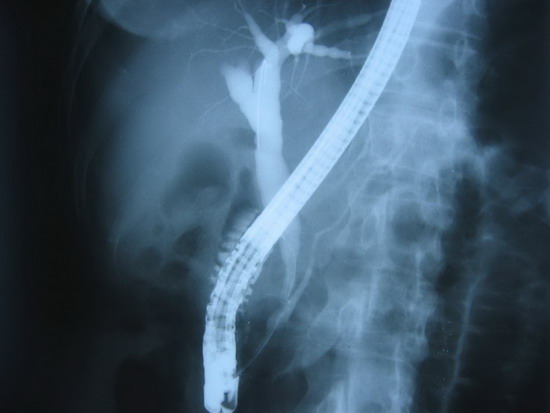

ERCP(2006年5月25日):

乳头插管成功后造影,见胰胆管汇流异常,为B-P型,共同段长约1.5厘米,共同通道膨大,乳头开口狭窄,近端胆总管轻度扩张,横径约1.2厘米。留置导丝后行共同段括约肌切开0.8厘米,插入取石球囊,充气后拉出一些存在于扩张的共同段内的灰白色絮状物。